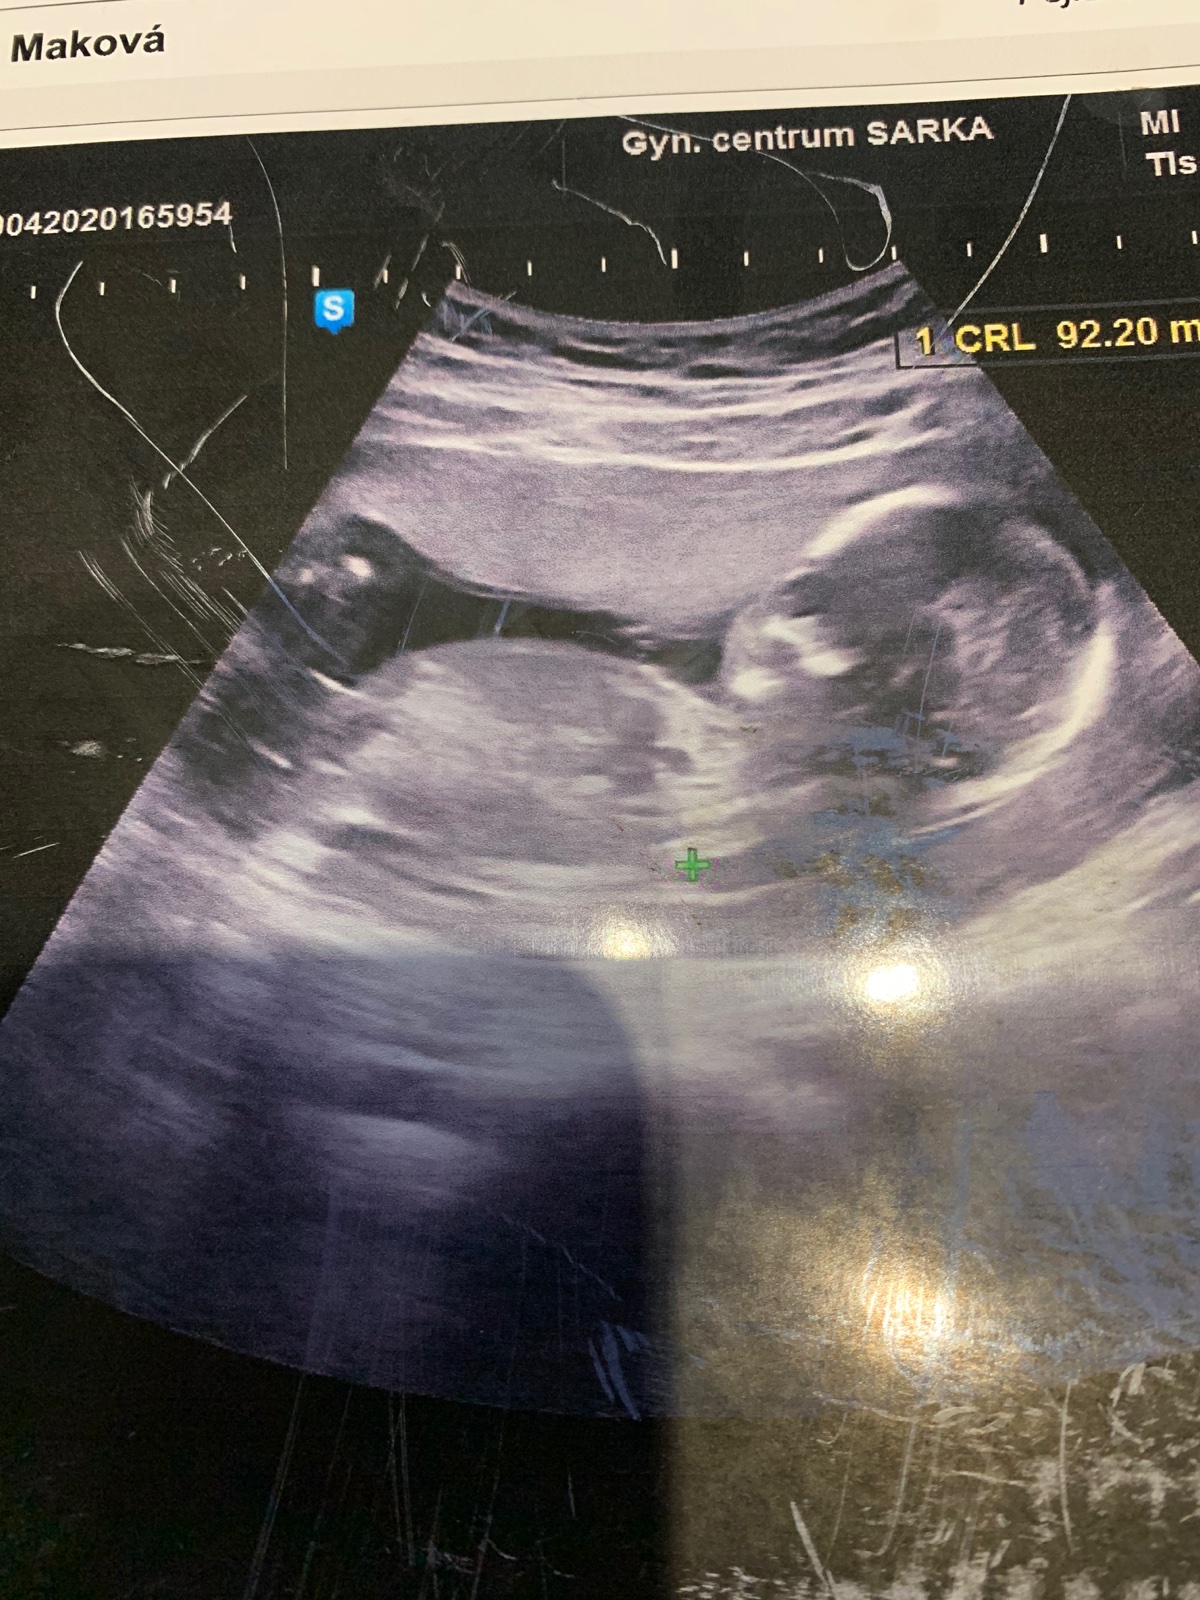

Ahoj maminky,určitě jste tady dost zkušené..pozorovala jsem už podobné diskuze,tak se taky obracím 😁 vidíte tam chlapečka nebo holčičku? Predevcirem na ultrazvuku mi doktorka říkala, ze na 70% kluk ale ze ji muže zmást pupeční šňůra,ze si mám spíše počkat do 20 týdne,ale ze je to spíše chlapeček. Na obrazovce jsem ale neviděla okolo nožicek žádný pytlík nebo něco co by bylo podobné varlatám,spis jen takový malinký šourek.. Co myslíte vy?? Tady to sice nejde moc poznat ale snad se něco překvapivého dozvim😁 Samozřejmě je mi to jedno,hlavně ze je zdravoucke❤️

Bohuzel to z toho nejde moc poznat 🙂 ale kdyz to srovnam s nasim ultrazvukem taky bych rekla chlapecek 🙂 nam ho bohuzel potvrdily az v 21tt na 2 screeningu... Drive taky ani tuk :D a souhlasim ze 3D je spolehlivy tam nam ho potvrdily opet podruhe a potreti jeste jednou ve 38tt v porodnici na kontrole 🙂)) takze bych jeste pockala do toho 2 screeningu a i dr mi rikal ze ten je nejpresnejsi a je to tam videt nejlepe ❤

I kdyby se tady na to nasel nejaky odbornik, tak na tehle fotce to neni absolutne kde videt.

@marinagilanyi počkala bych na 3D,jestli ho budou dělat,to je jistější. Ale tenhle snímek nezabírá moc dobře tu "ostře " sledovanou oblast 😁takže já tam nic nevidím. Náš malý měl pytlíka znát už od 12tt,jsem se schválně koukla a na další genetice to už jen potvrdili ,to jsem byla už po tom 20tt,jestli si dobře pamatuji